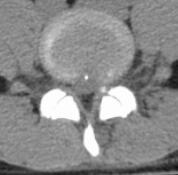

针对该患者的诉求,张昊主任与其团队进行了反复的讨论并分析小王的问题,首先,小王才15岁,但腰椎间盘突出明确并伴有椎体后缘离断,神经受压明显,导致下肢疼痛、麻木,严重影响日常生活和学习,经过一段时间保守治疗,仍反复,并且越来越明显了,因此针对青少年的腰椎间盘突出症患者治疗方面该如何定夺呢?张昊主任分析,结合该患者的特殊性,又要考虑患者以后的影响,把相关治疗方案以及相应的风险等事宜详细告知陈女士,最终在微创理念下采用脊柱内镜下腰椎间盘摘除技术为小王进行手术,手术切口1cm,术后症状缓解,恢复良好,效果非常满意,第二天顺利出院。

术后影像